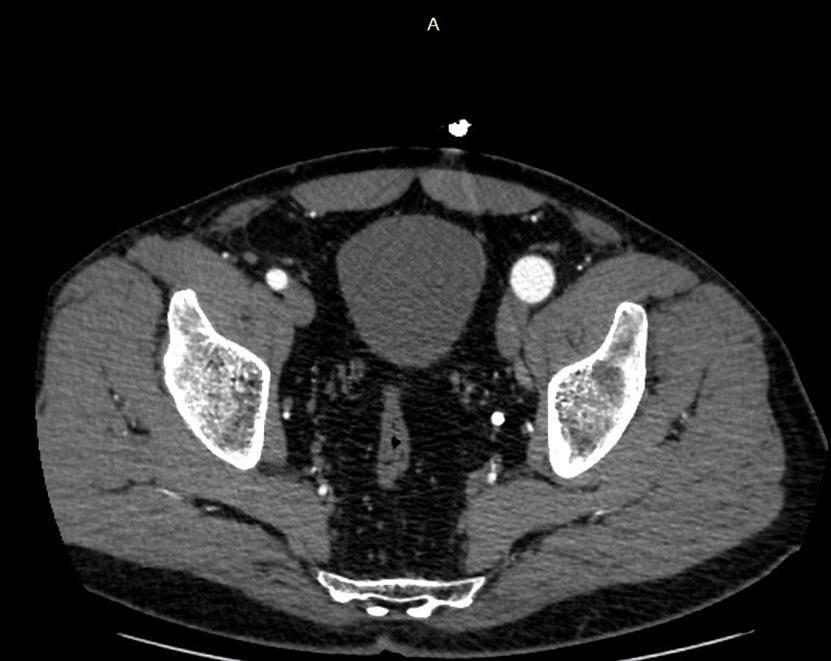

По результатам ЭХОКГ выявлена значимая перегрузка правых отделов сердца. Во время КТ ангиографии врачи обнаружили артерио-венозное соустье в области подколенной ямки (патологическое сообщение между артерией и веной, приводящее к перегрузке сердца). За годы функционирования этой артерио-венозной фистулы произошло расширение артерио-венозной стенки, что привело к значительному расширению артерии. Это грозило разрывом аорты или развитием аневризмы сердца.